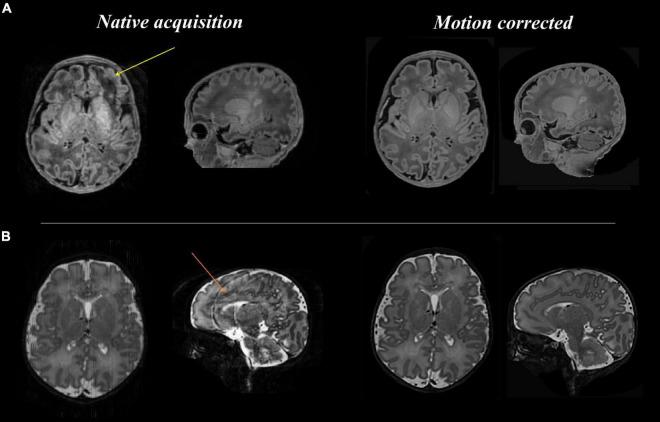

The Developing Human Connectome Project has created a large open science resource which provides researchers with data for investigating typical and atypical brain development across the perinatal period. It has collected 1228 multimodal magnetic resonance imaging (MRI) brain datasets from 1173 fetal and/or neonatal participants, together with collateral demographic, clinical, family, neurocognitive and genomic data from 1173 participants, together with collateral demographic, clinical, family, neurocognitive and genomic data. All subjects were studied and/or soon after birth on a single MRI scanner using specially developed scanning sequences which included novel motion-tolerant imaging methods. Imaging data are complemented by rich demographic, clinical, neurodevelopmental, and genomic information. The project is now releasing a large set of neonatal data; fetal data will be described and released separately. This release includes scans from 783 infants of whom: 583 were healthy infants born at term; as well as preterm infants; and infants at high risk of atypical neurocognitive development. Many infants were imaged more than once to provide longitudinal data, and the total number of datasets being released is 887. We now describe the dHCP image acquisition and processing protocols, summarize the available imaging and collateral data, and provide information on how the data can be accessed.

人类连接组发育项目创建了一个大型开放科学资源,为研究人员提供数据,以调查围产期典型和非典型的大脑发育情况。该项目收集了1173名胎儿和/或新生儿参与者的1228个多模态磁共振成像(MRI)脑部数据集,以及1173名参与者的相关人口统计学、临床、家庭、神经认知和基因组数据。所有受试者在出生时和/或出生后不久,在一台MRI扫描仪上使用专门开发的扫描序列进行研究,这些序列包括新型运动耐受成像方法。成像数据辅以丰富的人口统计学、临床、神经发育和基因组信息。该项目现在正在发布大量新生儿数据;胎儿数据将另行描述和发布。此次发布包括783名婴儿的扫描数据,其中:583名是足月出生的健康婴儿;还有早产儿;以及非典型神经认知发育高危婴儿。许多婴儿接受了多次成像以提供纵向数据,此次发布的数据集总数为887个。我们现在描述dHCP图像采集和处理方案,总结可用的成像和相关数据,并提供有关如何获取这些数据的信息。